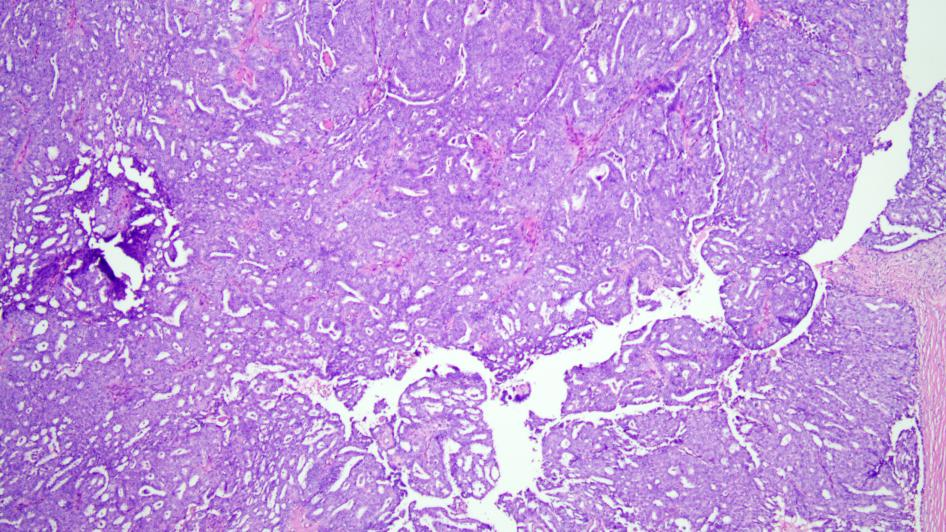

随后,甲乳胸外科为他进行左侧胸壁肿物切除术,

术后送检肿物组织至我院病理科,

检查结果提示为乳腺导管内乳头状原位癌。